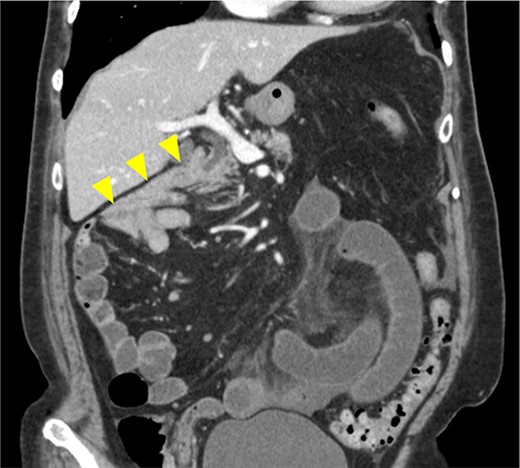

An 86-year-old woman with no prior abdominal surgeries was admitted to our hospital complaining of constant abdominal pain with an acute onset of 8 hr duration. The physical examination revealed tenderness of the lower abdomen. The laboratory test results were unremarkable, except for elevated lactate (3.0 mmol/l) and leukocyte counts (14 400/μl). Contrast-enhanced computed tomography (CT) revealed a closed-loop obstruction of the hypo-enhancing small bowel in the left lower abdominal quadrant, which suggested a strangulated bowel obstruction (Fig. 1). The duodenum did not form a horizontal limb and ran caudally to the jejunum (Fig. 2). The duodenojejunal flexure was abnormally located in the right upper abdominal quadrant, which suggested an intestinal malrotation. Sac-like capsulated small-bowel loops were barely visible.

Image from enhanced CT. Contrast-enhanced CT shows the absence of a horizontal duodenal leg and the duodenum running caudally to the jejunum (arrowhead).